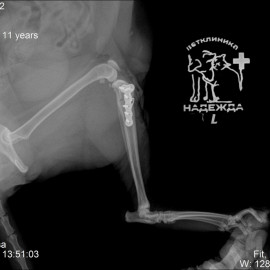

Рентгенологический снимок после проведенной операции.